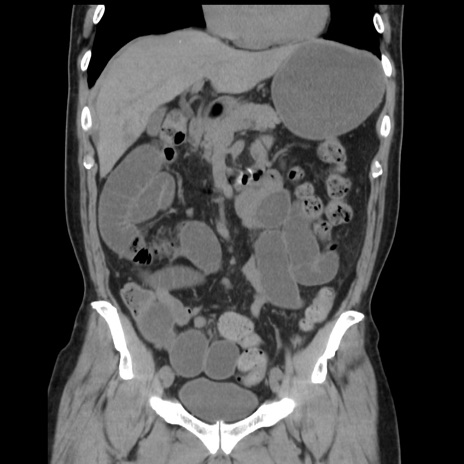

症例16(冠状断像)

【症例】 70歳代男性

【主訴】 腹痛、嘔吐

【現病歴】 約1ヶ月前より間欠的に腹痛と嘔吐あり、当院消化器内科を受診したところCTで多発する肝臓のLDAを指摘され、精査中であった。以降は消化器症状は安定していたが、2日前より嘔気と腹痛があり、同日より排便・排ガスが消失した。改善認めず、 本日、救急外来を受診した。

【既往歴】 大腸ポリープ切除後。

【身体所見】意識清明・会話良好、BT 36.3℃、BP 127/80mmHg、 P 80bpm、腹部:膨満あり、平坦・軟、上腹部正中および下腹部正中に圧痛あり、反跳痛なし、筋性防御なし。

【データ】WBC 7200、CRP 0.77